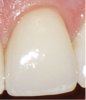

The BEWE is a scoring system that evaluates the most severely affected surface in each sextant, recording one of the four-level scores as follows30: 0 = no erosive tooth wear (Figure 8); 1 = initial loss of surface texture (Figure 9); 2 = distinct defect, hard-tissue loss <50% of surface area (Figure 10); 3 = hard-tissue loss ≥50% of surface area (Figure 11). (Scores 2 and 3 often involve dentin.) After all sextants are assessed, the sum of scores provides the risk level of each patient and may help guide the design of a professional management program for the patient.

Fig 8. BEWE scoring system: score 0 = no erosive tooth wear (Fig 8); score 1 = initial loss of surface texture (Fig 9); score 2 = distinct defect, hard-tissue loss <50% of surface area (Fig 10); score 3 = hard-tissue loss ≥50% of surface area (Fig 11)

Figure 9